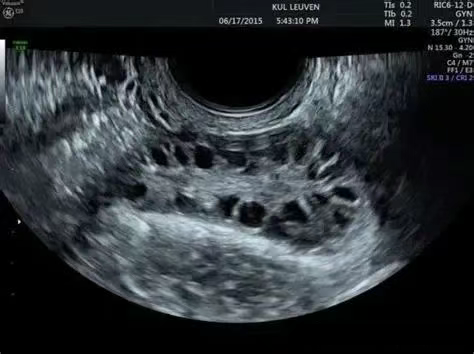

多囊卵巢超声表现

尤其擅长处理多囊卵巢综合征(PCOS)、反复种植失败等疑难情况。

针对陈姐的PCOS体质,吉国医生制定了极其细致的促排方案。用药剂量根据她每天的激素水平和B超监测结果进行动态微调。